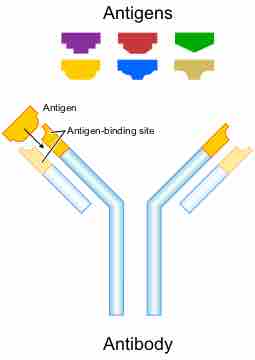

A region at the tip of the antibody protein is very variable, allowing millions of antibodies with different antigen-binding sites to exist.

Complex genetic mechanisms evolved which allow vertebrate B cells to generate a diverse pool of antibodies from relatively few antibody genes.

The clonal selection hypothesis is a widely accepted model for the immune system's response to infection.

Isotype class switching is a biological mechanism that changes a B cell's production of antibody from one class to another.